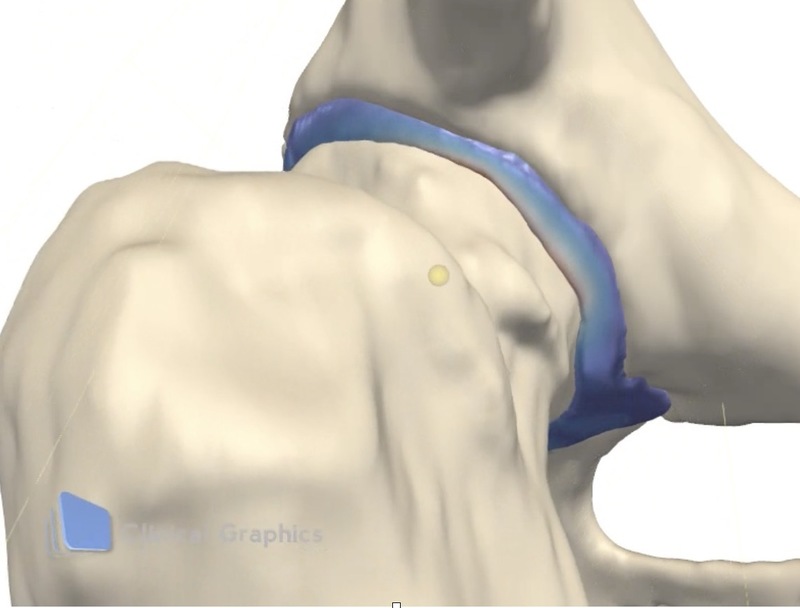

Femoroacetabular impingement (FAI)とは

・股関節と骨盤の解剖学的な骨形態異常により、大腿骨近位部と骨盤(主に寛骨臼)が異常に接触することでおこる病態。[Ganz 2003 CORR]

・この異常接触によって、結果的に関節唇損傷、軟骨損傷が引きおこり、変形性股関節症へと進行することもある。

股関節唇の役割